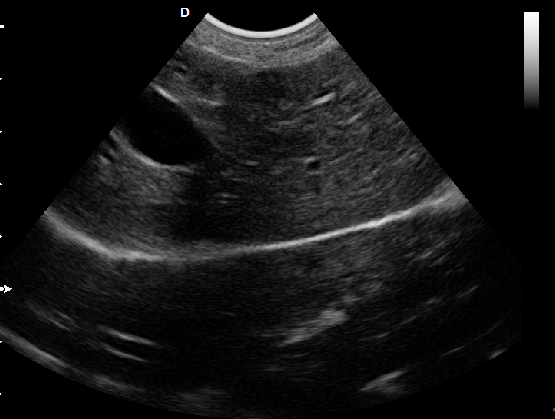

脊椎檢查:

脊柱裂的預(yù)防和確診,一般在動(dòng)物懷孕以后定期給動(dòng)物做超聲檢查,通過(guò)超聲、超聲檢查可以早期發(fā)現(xiàn)動(dòng)物胎兒是否合并了脊柱裂或是神經(jīng)管閉合不全。